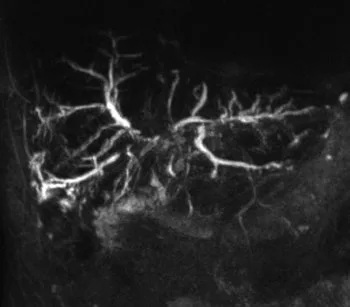

Figure 1. Patient exploré par bili-IRM pour une suspicion de migration lithiasique.

A. Cette coupe de bili-IRM 2D montre de multiples lithiases vésiculaires, ainsi qu’un calcul du bas cholédoque (tête de flèche).

B. Sur cette projection cholangiographique « MIP » issue d’une acquisition 3D en coupes fines, le calcul cholédocien est trop

petit au sein de cette VBP dilatée, et il n’est pas correctement visualisé. En cas de bili-IRM 3D, l’analyse de chacune des coupes

fines du volume est impérative. Ainsi, contrairement à la projection « MIP », la coupe fine passant par le cholédoque permet

de bien montrer le calcul (C)